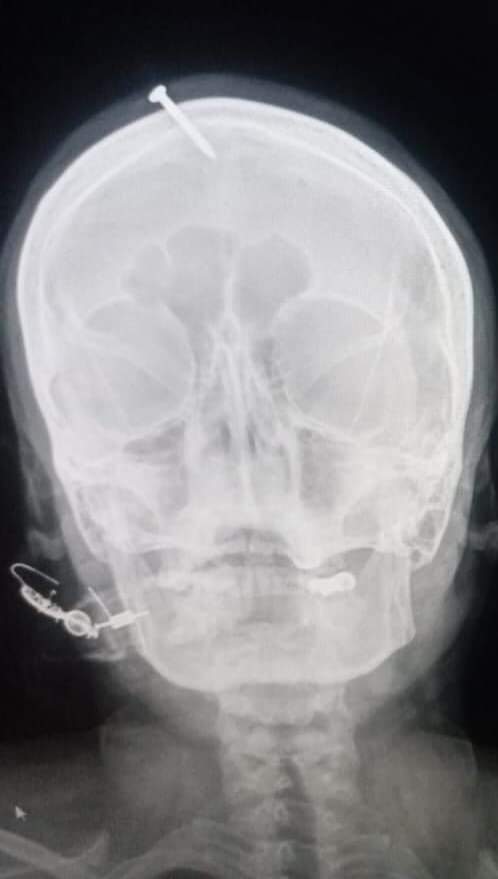

ایکسرے سے معلوم ہوا کہ پانچ سینٹی میٹر (دو انچ) کی کیل خاتون کے ماتھے کے اوپری حصے میں ٹھونکی گئی تھی، لیکن اس سے ان کے دماغ کو کوئی نقصان نہیں پہنچا تھا۔